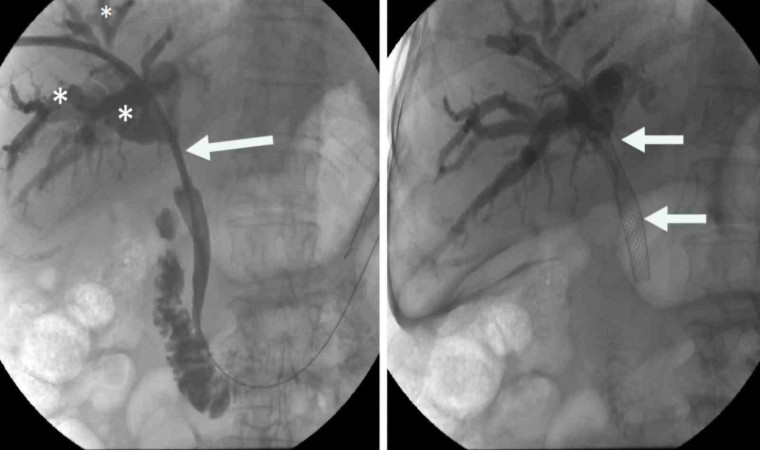

Prof. Dr. Ahmet Memiş’in önderliğinde uygulanan bu yenilikçi yöntem, endoskopik teknikleri ve iğne ile giriş yöntemlerini tek bir operasyonda birleştiriyor. Bu sayede, daha önce tedavisi çok zorlu kabul edilen karmaşık safra yolu problemleri artık daha etkili ve minimal invaziv bir şekilde tedavi edilebiliyor. Hibrit yaklaşımların en önemli avantajlarından biri, hastaların bedenine minimum düzeyde zarar vermesidir. Büyük cerrahi kesilerin yerine, endoskopik, gastro ve girişimsel radyoloji yöntemler kullanılarak, iğne deliği kadar küçük girişimlerle operasyonlar gerçekleştiriliyor. Bu da hastaların ameliyat sonrası ağrılarını azaltıyor, enfeksiyon riskini düşürüyor ve hastanede kalış sürelerini kısaltıyor.

Prof. Dr. Ahmet Memiş, “Hibrit yaklaşım, sadece tedavi değil, aynı zamanda tanı sürecinde de önemli avantajlar sunuyor. Hekim, hastanın vücuduna dokunmadan, radyolojik görüntüleme teknikleriyle hastalıklar daha hızlı ve doğru bir şekilde tespit ediliyor. Bu da tedavi sürecinin daha etkin bir şekilde planlanmasına imkan sağlıyor. Farklı disiplinlerden uzman hekimlerin bir araya gelerek oluşturduğu sinerji, karmaşık safra yolu sorunlarında başarı oranını önemli ölçüde artırıyor. Bu sayede, hastalar daha hızlı iyileşme göstererek günlük yaşamlarına daha kısa sürede dönebiliyor. Geleneksel cerrahi yöntemlerde uzun iyileşme süreleri ve yoğun ağrılar yaşanırken, minimal invaziv yaklaşımlar sayesinde bu sorunlar ortadan kalkıyor. Hastalar, operasyon sonrası çok daha kısa sürede taburcu oluyor ve gündelik aktivitelerine hızla dönebiliyorlar. Bu da hem hasta konforunu artırıyor hem de sağlık sisteminin üzerindeki yükü hafifletiyor” dedi.